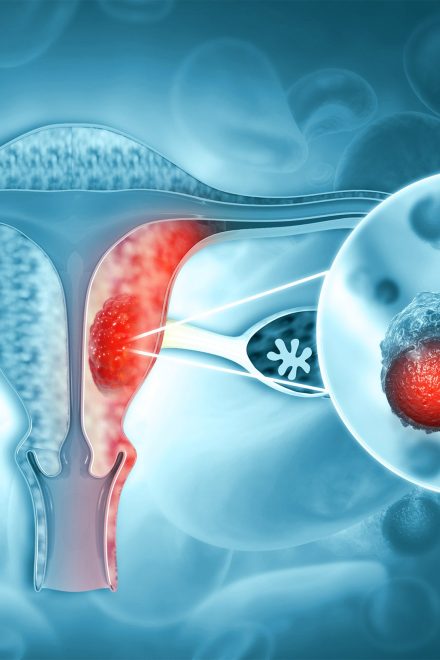

Model predicts risk of endometrial cancer

Model predicts risk of endometrial cancer